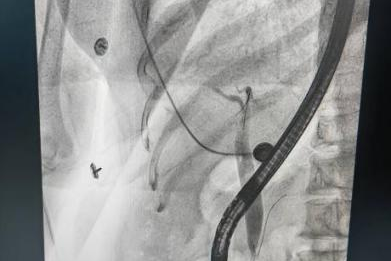

最近,河南中医药大学第三附属医院就遇到了这样一位"愁坏了"的患者:胆总管、肝总管还有左右肝管全都扩张了!术中明确诊断为胆总管下段狭窄伴结石。这就好比家里的下水管道突然集体"变粗",不仅影响正常"排水",还可能藏着"堵塞物"(结石),再拖下去,麻烦可就大了!不过别慌!

河南中医药大学第三附属医院消化内镜中心的李严生主任团队,直接掏出了"王牌技术"——经内镜逆行性胰胆管造影术(ERCP)顺利完成胆管狭窄球囊扩张术及取石操作。手术过程顺利,术后情况稳定,恢复良好,已顺利出院!该例手术的成功开展,可不单单是治好了一位患者,它是对获得河南省医疗卫生服务能力提升项目(消化内镜中心诊疗服务能力提升项目)的最好"点赞"!